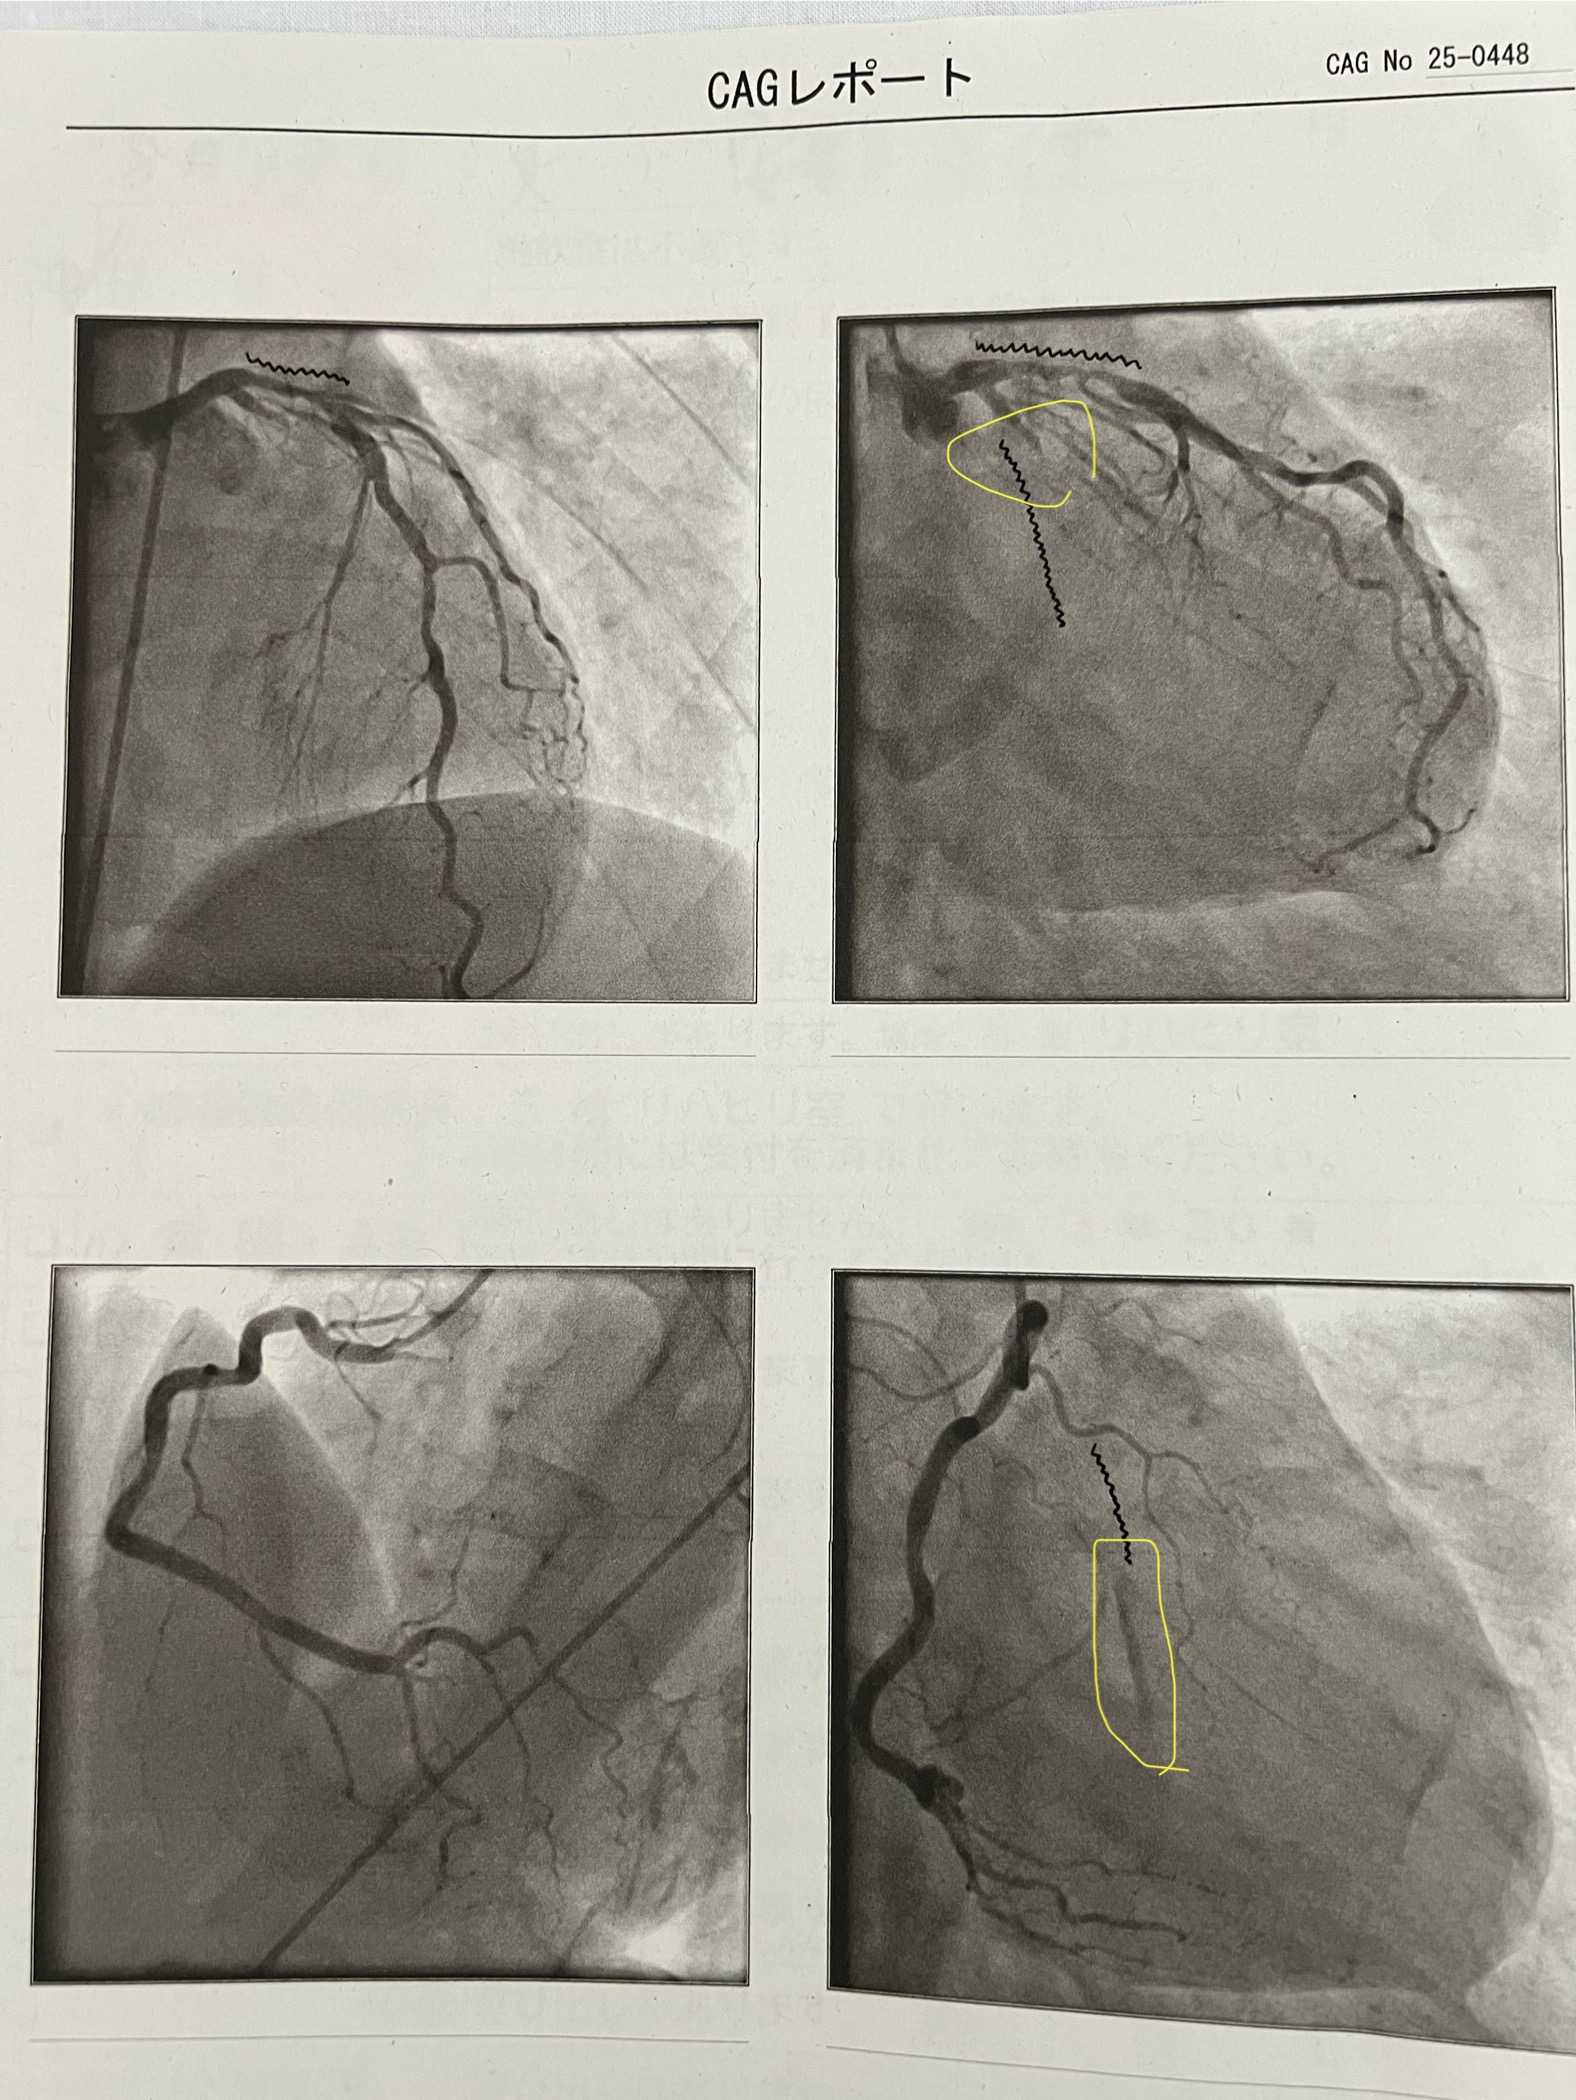

冠動脈カテーテルの結果

釣りに行きたいが仕事でなかなか行けない人のブログ

2025.08.21 09:48